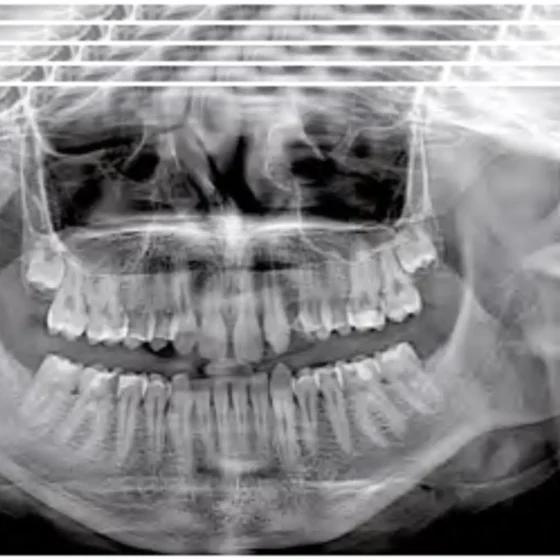

|GO2D expands the diagnostic range with its perfect panoramic view of teeth and exceptionally precise examinations. User-friendly, innovative, reliable. GO2D offers perfect OPG images enhanced by high performance acquisition and process.|

GO2D comes in two variant: with & without ceph. GO2D without ceph can perform PAN: adult (standard and eco), child, dentition, bitewings, SIN: PA and LL maxillary sinuses (right and left) and TMJ: Temporomandibular joint (2 x LL + 2 x PA) with mouth open and closed.